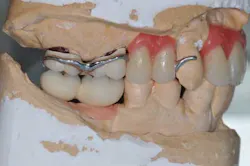

Figs. 5a and b: Impression for the RPD framework including the PFM frameworks and mounting

- Impressions and fabrication of the RPD and implant abutment metal frameworks.